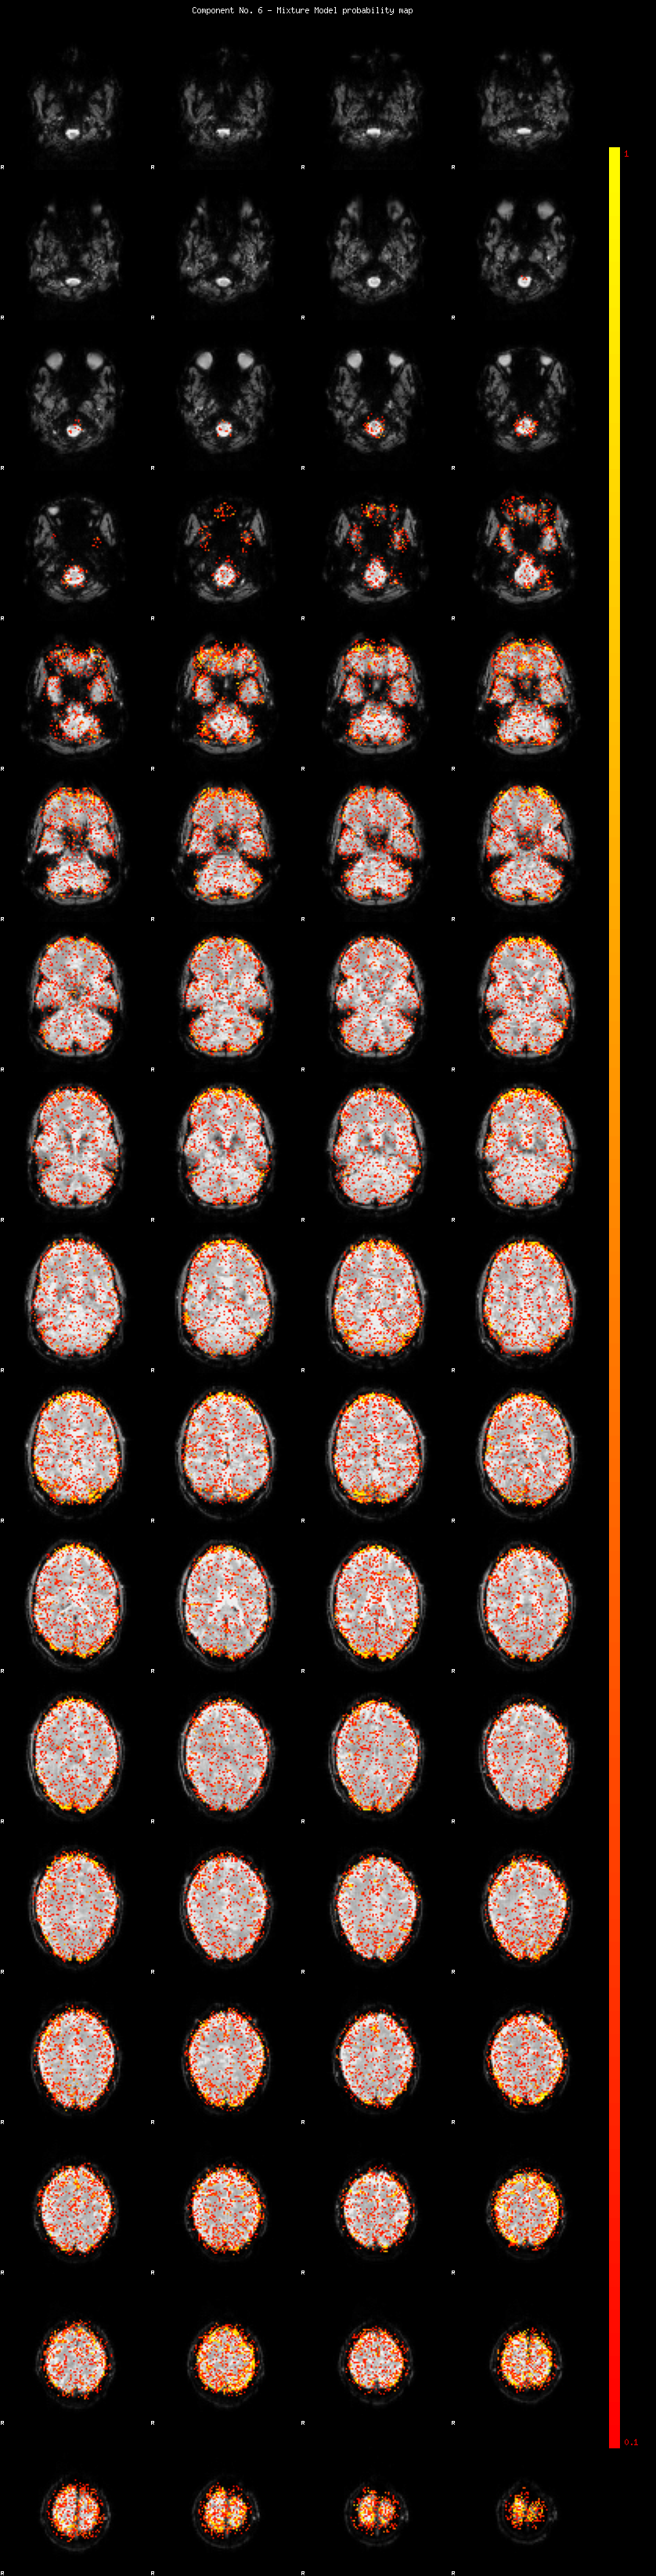

IC_6 Mixture Model fit

Means : 0.000000 2.233236 -2.341766

Vars : 1.000000 1.234664 1.479114

Prop. : 0.905979 0.035725 0.058296